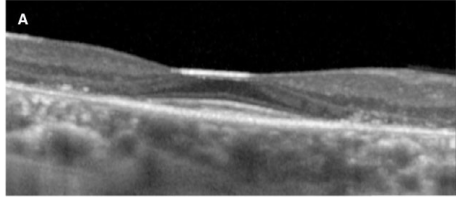

SD-OCT(Spectral-domain optical coherence tomography:光干渉断層計)…網膜表面構造を三次元的に画像化

「ヒドロキシクロロキン網膜症のスクリーニング - 日本眼科医会」( https://www.gankaikai.or.jp/tsushin/files/20170124_1.pdf)より